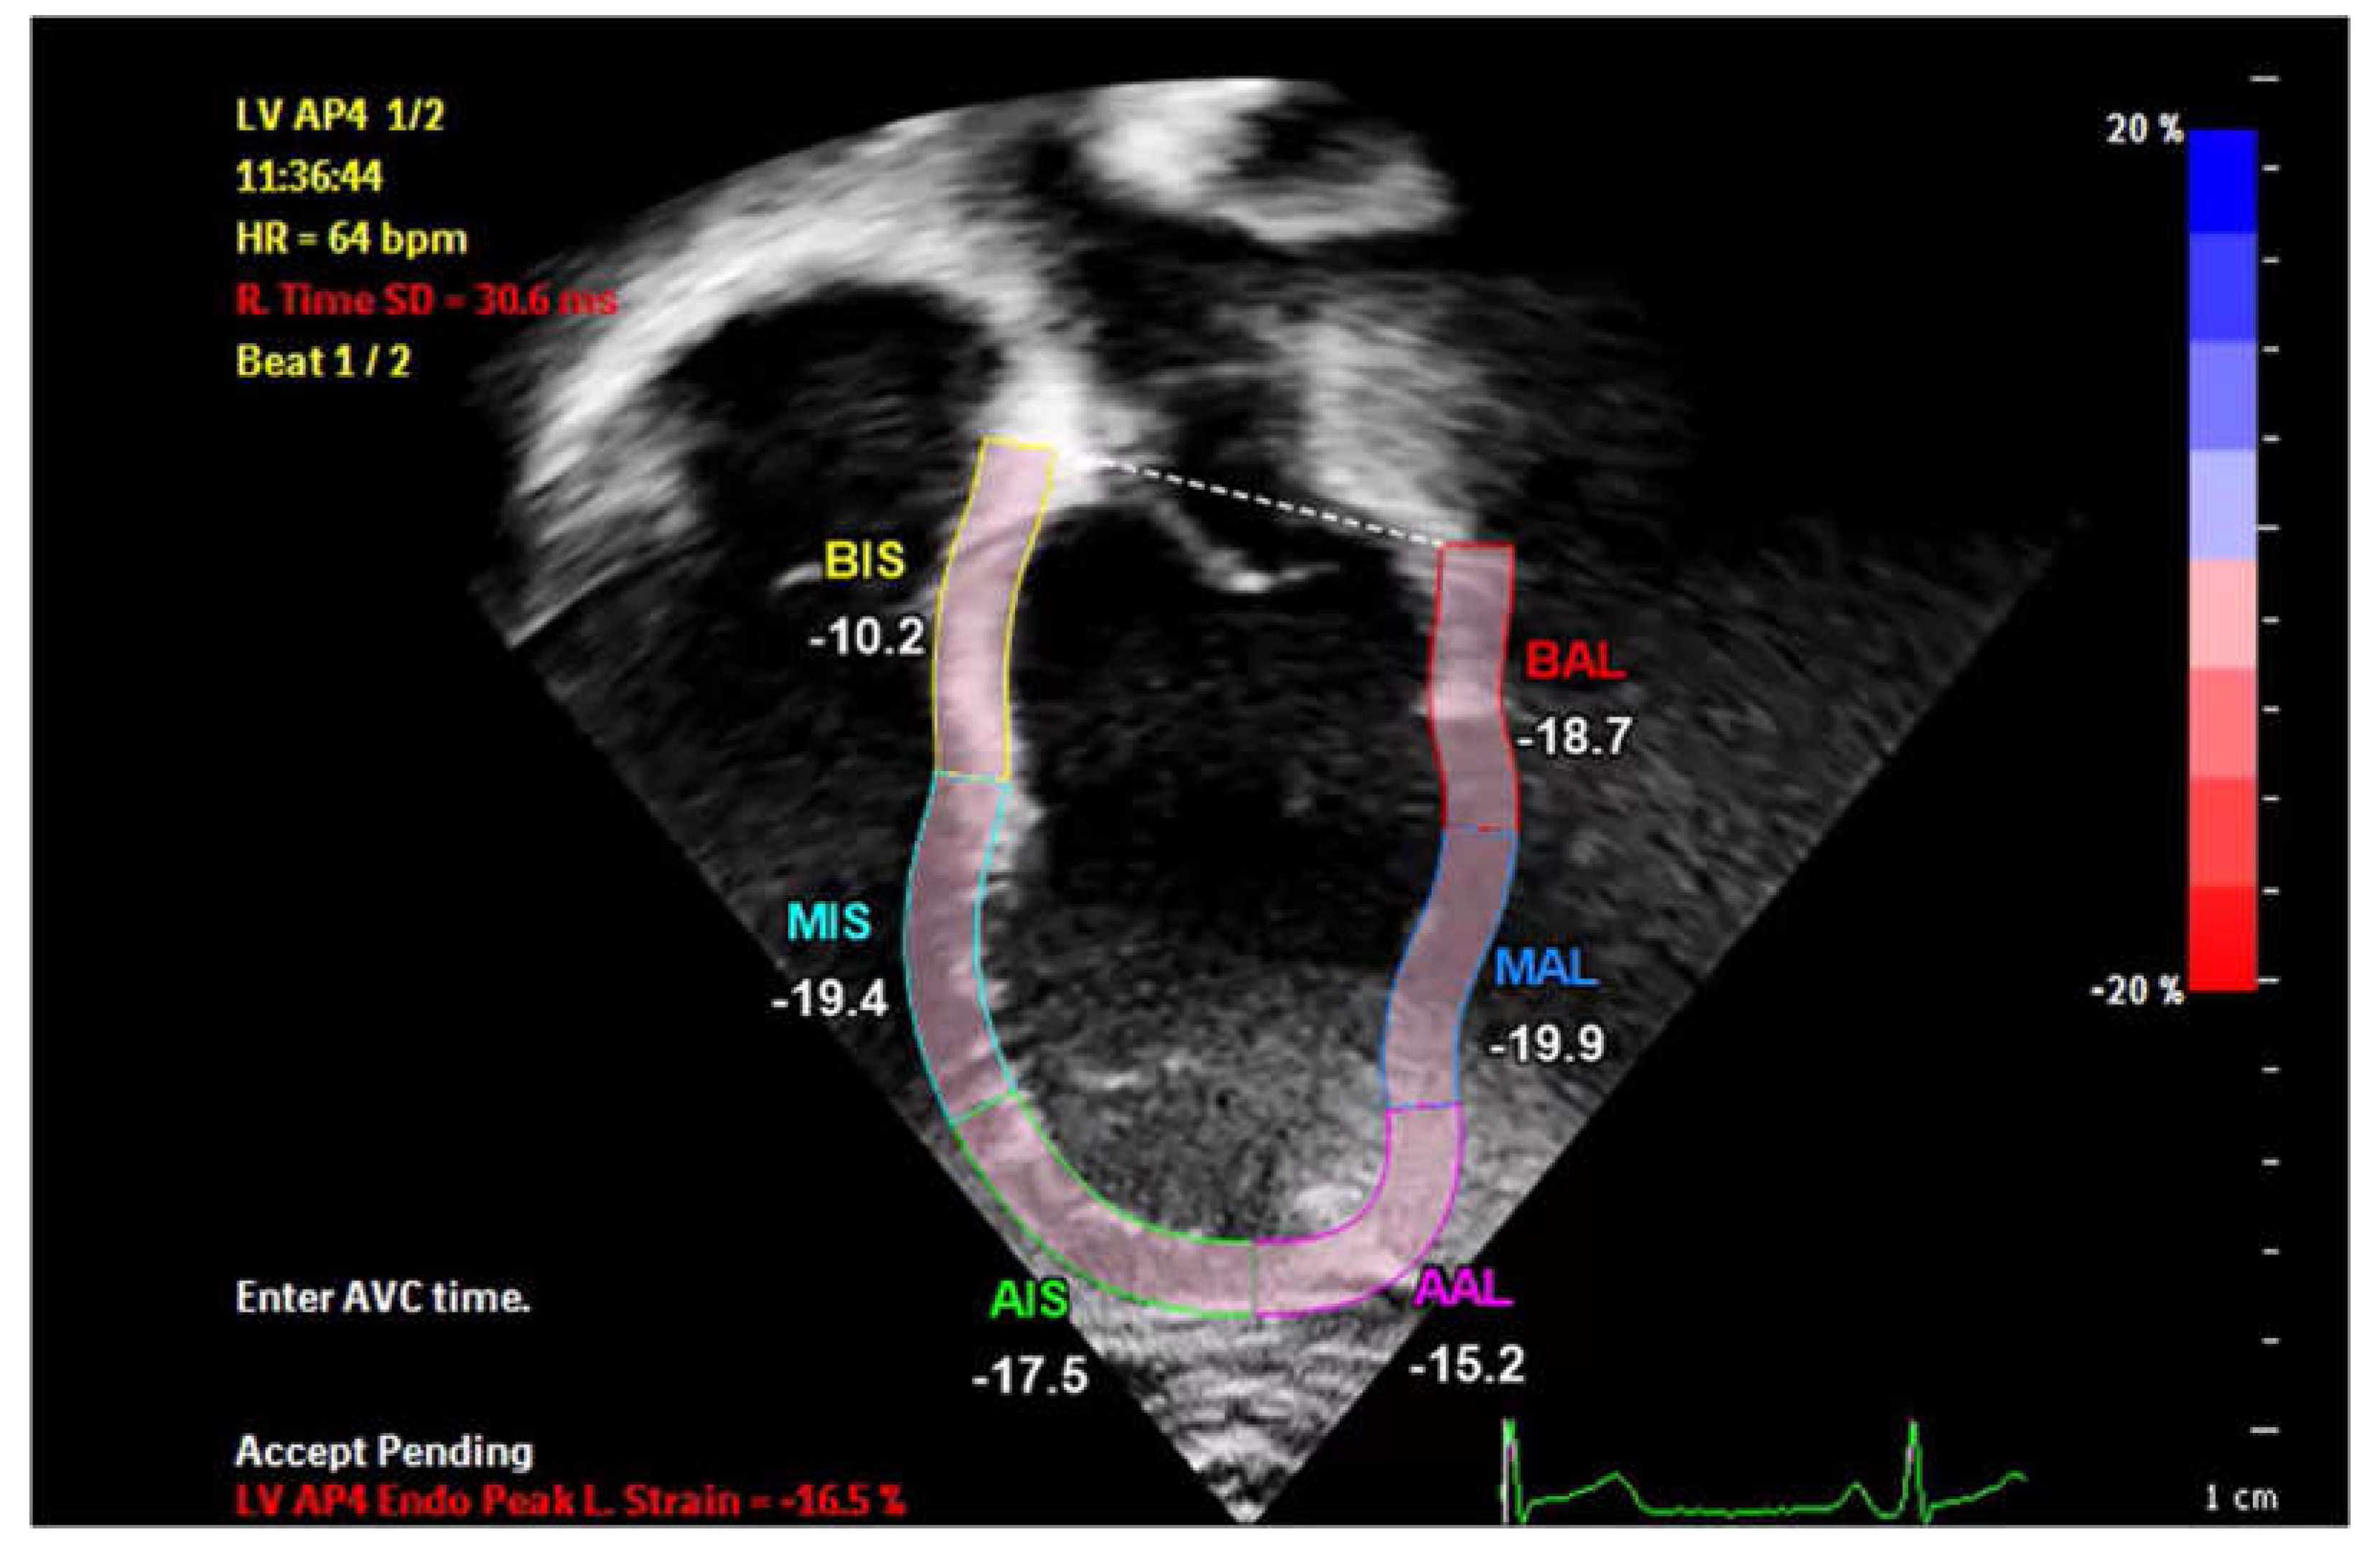

A 16-year-old male patient, presented with chest pain to the ER, alongside symptoms of upper respiratory infection, respiratory panel testing revealed to be adenovirus positive. The patient was hemodynamically compensated with unremarkable cardiac examination. Work-up for cardiac causes of chest pain revealed elevated serum Troponin T and non-specific elevation of the ST segment in the anteroseptal leads (juvenile repolarization pattern-Figure 3A), patient was admitted for observation, and for serial Troponin T testing, which showed persistent elevation at 800 ng/dL (Figure 3B). Following the persistence of manifestations and the lagging Troponin T levels, we performed a speckle-tracking examination of the patient, which, once again displayed a segmental affection of the basal septal part of the LV (Figure 4). At this stage, a dose of intravenous immunoglobulins was administered to the patient, after which there was a progressive decrease in cardiac enzyme levels, normalizing 15 days approximately after the dose. (Figure 3B)

Figure 4. Basal Septal affection by 2 D speckle tracking in Case 2 .